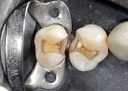

Joe Cha #20 pre-op